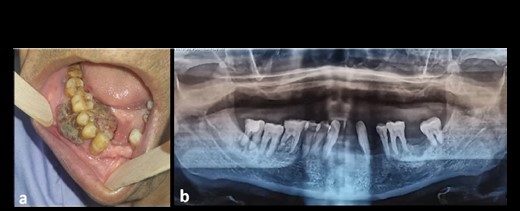

We present the case of a 73-year-old man with no significant previous medical history. He experienced purple swelling in the right mandibular gingiva (Fig. 1a). The clinical examination was normal. However, a panoramic radiograph revealed bone resorption around the crowns of the 44 and 46 teeth (Fig. 1b). Further examination, including an extraoral examination and TAP CT scan, did not reveal any other mass or lymphadenopathy.

(a) Clinical image of an intraoral EA localized at the mandibular gingiva with extensive red-purple appearance; (b) orthopantomographic image showing resorption of the mandibular bone around the crown of the 44 and 46 teeth.